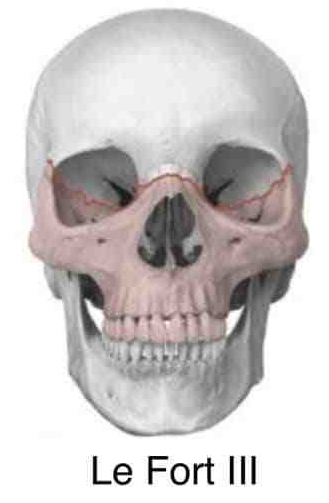

打在上颌骨上可能发生什么骨折呢?

第三型骨折(LeFort Ⅲ型骨折)的骨折线也通过鼻骨、泪骨,但横过眶窝及颧骨上方,向后到上颌骨后壁,使上颌骨、颧医学整理骨与颅骨完全分离,因此又称为颅面分离。.

上颌骨Le Fort 骨折分型对临床诊治具有一定指导作用;除了共同临床表现之外,各型上颌骨Le Fort 骨折都具有其独特的临床表现,如:Le Fort Ⅱ型骨折会出现鼻及眶下缘的变形,常有鼻腔侧壁及上颌窦的损伤等,Le Fort Ⅲ型骨折则常形成颅面分离,使面中部凹陷、变长等;这些不同的临床表现对临床诊断有重要参考意义;各型上颌骨Le Fort 骨折在治疗上也具有一定特点,如Le Fort Ⅰ型骨折手术时多数只需采用口内前庭切口就能取得良好的疗效;而Le Fort Ⅱ、Ⅲ型骨折则多需口内前庭切口和头皮冠状切口联合应用才能获得满意的显露效果;再如Le Fort Ⅲ型骨折常伴有颅脑损伤和颅底骨折,处理时应注意颅脑损伤的诊治。